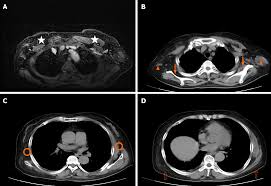

What Does Breast Cancer Look Like On A Ct Scan / Breast Cancer Radiation Planning Imaging Technology News - High risk of breast cancer.. Learn the stage of your cancer. Your doctor may recommend a breast mri scan if you have a diagnosis of breast cancer to determine the extent of the cancer. At left is a ct scan, while the center image is from a pet scanner. If your doctor suspects that you have cancer near your abdomen, they may recommend an abdomen ct scan. Ct, mri, and pet scans can also tell if your cancer spread.

Finding breast lumps and seeing change in the size and shape. Ct scans can help doctors: This test is most often used to look at the chest and/or belly (abdomen) to see if breast cancer has spread to other organs. Leak or rupture of a breast implant. With cancer cells, they appear as bright spots due to its higher metabolic rate compared to normal cells. A ct scan is a safe test for most people but like all medical tests it has some possible risks. As you probably know, a ct scan is one of several imaging techniques—this one primarily for looking at organs. Ct scans can be misread or misinterpreted. This helps radiologists identify areas where cells are suspiciously active, which can indicate cancer. As other answers have stated, what ct (and mri, and ultrasound) can show is the overall size of the lymph nodes, and in some cases how much blood supply they have. They may also use it to learn more about the cancer after they find it. Pet scan for breast cancer. If you have a condition like cancer, heart disease, emphysema, or liver masses, ct scans can spot it or help doctors see any changes.

Cureus Excellent Response With Ado Trastuzumab Emtansine In A Patient With Relapsed Metastatic Breast Cancer Presenting With Pulmonary Lymphangitic Carcinomatosis from assets.cureus.com This helps radiologists identify areas where cells are suspiciously active, which can indicate cancer. Imaging and lobular breast cancer. This tracer can help identify areas of cancer that an mri or ct scan may not show. Areas of tumor tend to pick up the labeled compound and show up as foci of increased activity either bright or dark spots depending how the image is displayed. Finding breast lumps and seeing change in the size and shape. Lobular breast cancer can be more difficult to see on imaging and scans. (1) gary ulaner, md, phd, facnm. What does breast cancer look like?

Imaging and lobular breast cancer. When a breast cancer has been diagnosed, some people have a ct scan of their chest and tummy (abdomen) to stage the breast cancer. 4.9k views reviewed >2 years ago What does breast cancer look like? Your doctor and radiographer make sure the benefits of having the test outweigh these risks. Controversy continues to surround the question of whether ct and bone scans should be standard in evaluating patients for these metastases, or whether integrated pet/ct scanning might. To help you prepare, here's a look at what to expect. With cancer cells, they appear as bright spots due to its higher metabolic rate compared to normal cells. It is common for patients to receive a diagnosis for cancer of unknown primary. Ct scans can be misread or misinterpreted. The big problem with imaging is that we know, with certainty, that we can't usually. Combining a pet scan with an mri or ct scan can help make the images easier to interpret. As you probably know, a ct scan is one of several imaging techniques—this one primarily for looking at organs.

Small Cell Lung Cancer With Metastasis To The Breast A Case Report And Review Of The Literature from www.jscimedcentral.com Controversy continues to surround the question of whether ct and bone scans should be standard in evaluating patients for these metastases, or whether integrated pet/ct scanning might. Breast mri is most often used to screen for breast cancer in women thought to have a high risk of the disease. Identify the correct area for. Imaging tests usually can't tell if a change has been caused by cancer. As you probably know, a ct scan is one of several imaging techniques—this one primarily for looking at organs. Your doctor may recommend a breast mri scan if you have a diagnosis of breast cancer to determine the extent of the cancer. I have my yearly check up in a few weeks time. A patient undergoing a breast ct scan will lie face down on a table that is slid into a scanner that takes photographs of the patient's chest area.